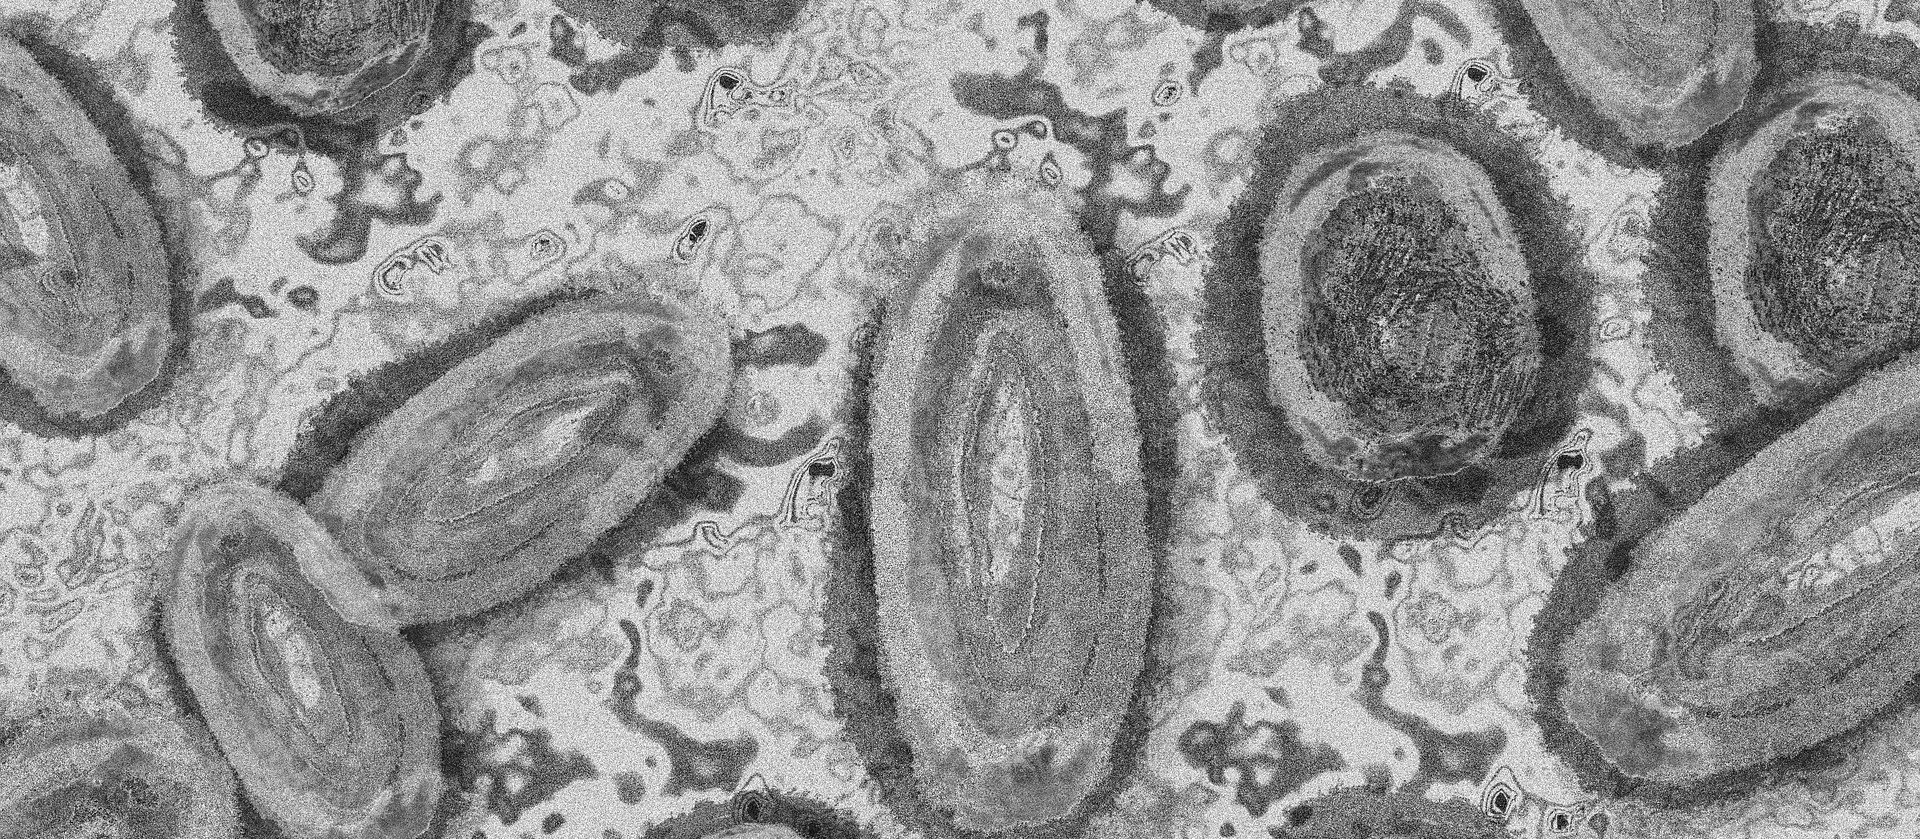

Imagem Ilustrativa/Representação abstrata do vírus da varíola/Gerd Altmann/Pixabay

A Monkeypox, conhecida como varíola dos macacos, é uma doença viral que pode ser transmitida principalmente por contato de pele com pessoas contaminadas. Entre os principais sintomas está a lesão de pele, além de febre, calafrios e dores musculares.